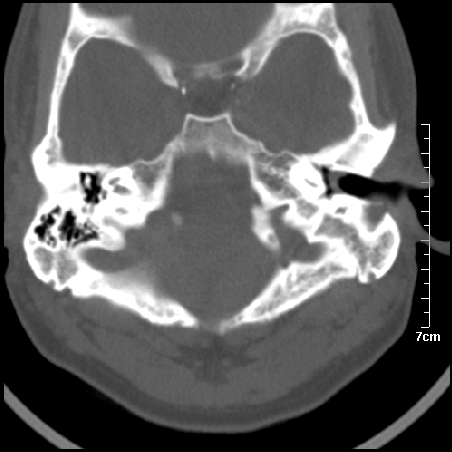

病例1

m/46y 头晕.耳鸣半月余 有乳突炎病史